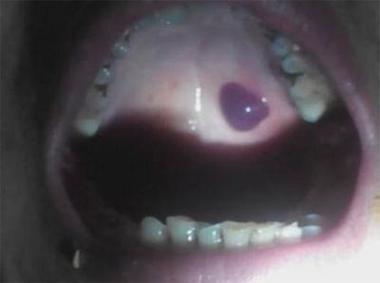

口腔内壁黑疙瘩是何问题?需警惕吗?

血管性病变:

- 海绵状血管瘤: 这是一种先天性血管畸形,可能表现为一个或多个深蓝色、紫色或黑色的柔软包块,按压时可能缩小,松手后恢复原状。